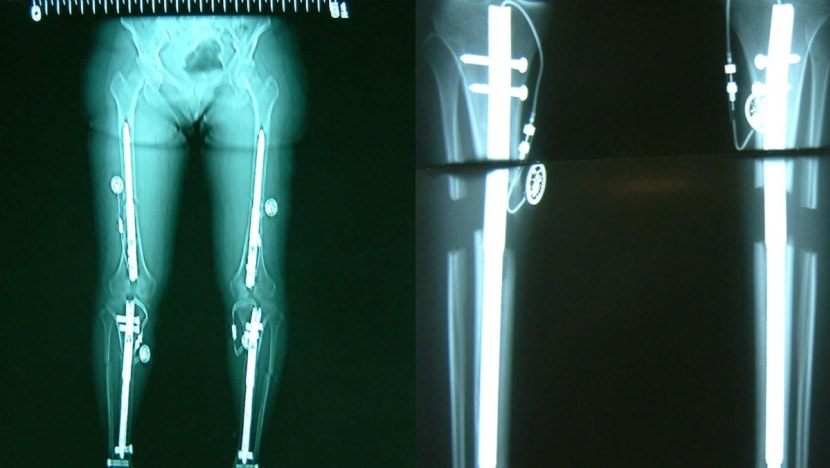

(Left) An X-ray of femur and tibia lengthening using internal lengthening rods and (right) an X-ray of tibia (shin bone) extension using an internal lengthening rod.

Newer methods using internal lengthening rods, devices that are implanted into the bone, have made the procedure “more comfortable and safer” than older methods using an external fixator, said Dr Singh.

For example, the Precice intramedullary limb-lengthening system, which uses a magnetic extension nail with a portable hand-held external remote controller, allows for precise control and has the ability to reverse the lengthening if necessary, he said.

With the older methods, an external scaffold is fitted into the patient’s leg using pins that are pierced through the skin, muscles and bones for a duration of about six to 12 months. This can cause significant pain and limitation of joint motion, and complications like pin-site infection are common, said Dr Singh.

While the techniques may differ, the principle for limb lengthening is the same: Bone is cut and gradually pulled apart at 1mm per day for new bone, nerves, vessels and muscles to form.